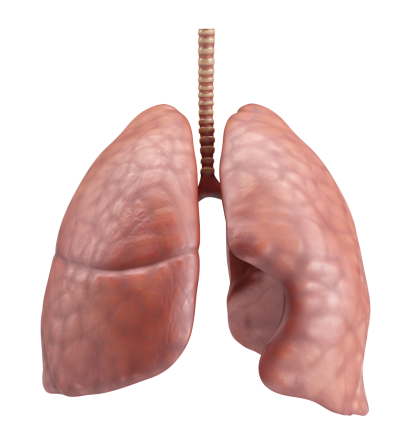

폐암은 폐에 비정상적인 암세포가 증식하여 덩어리를 형성하고 인체에 해를 미치는 것을 말합니다. 즉 폐에 생긴 악성종양을 말하며 폐 자체에 암이 발생하거나 다른 장기에서 생긴 암이 폐로 전이되어 발생합니다.

이러한 폐암이 생기면 어떤 증상이 나타나는지 폐암 초기증상에 대해 알아보도록 할게요.

폐암 초기증상